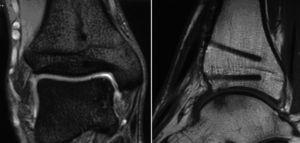

Las radiografías no mostraban ninguna evidencia de artrosis ni escalones a nivel del bloque óseo incorporado (fig. 16).

Figura 16